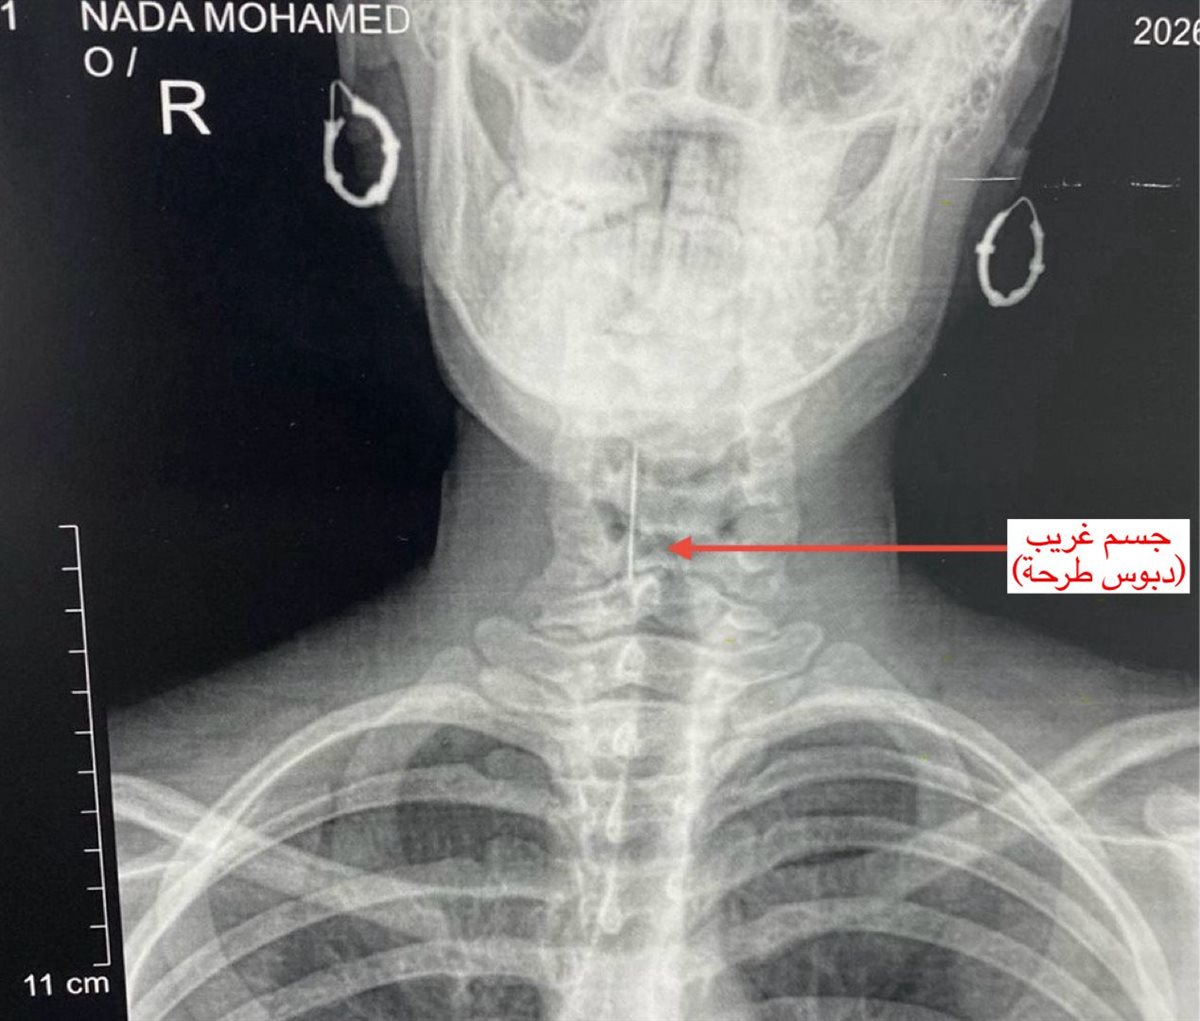

واستقبل قسم الاستقبال والطوارئ بالمستشفى المريضة وهي تعاني من آلام شديدة بالرقبة وصعوبة حادة في التنفس، حيث جرى على الفور إجراء الفحوصات والأشعة اللازمة التي كشفت عن استقرار الدبوس فى منطقة دقيقة بمدخل مجرى التنفس، ما شكّل خطورة على حياتها.